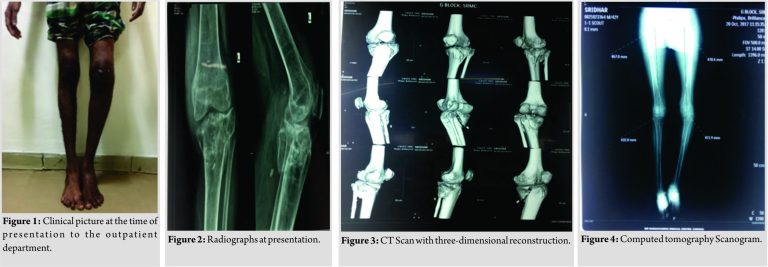

A 55-year-old gentleman, presented with complaints of pain over the left knee joint and inability to weight bear over his left leg for the past ten 10 months. The patient was apparently normal 10 months ago, when he had a history of slip and fall from 10 feet height at his workplace in the month of January 2017 and sustained close injury to his left knee. The patient developed pain and inability to weight bear over his left leg. The patient initially underwent native splinting for 6 months following the injury. As patient was not relieved of his symptoms following native splinting, patient came to Sri Ramachandra Medical College Porur for further management With complaints of pain, deformity, and unable to bear weight on left leg (Fig.1). There is no history of fever, loss of appetite or any other bone injury. The patient is not a known case of diabetic mellitus, Hypertension hypertension cardiac disease tuberculosis asthma epilepsy. The patient is not a smoker or an alcoholic. Examination revealed left lower limb appears to be shorter than the right lower limb. Muscle wasting was noted over the thigh and calf region. Healed abrasion scar present over the anterior aspect of the knee joint and the distal aspect of the leg. Dilated veins present over the posterolateral and the medial aspect of the knee joint. No popliteal fossa fullness was noted. Tenderness present over medial and lateral jointline Swelling present over the anterior aspect of knee joint. Bony mass is palpable over the anteromedial and lateral aspect of the knee. Broadening and thickening present over the anterior, medial, and lateral aspect of the knee joint. Abnormal mobility was noted. The Range range of Movement movement of the knee was 20 to –70°° with fixed flexion deformity of 20°.Further movements were painful. There was no neurovascular deficit noted.

Radiographs showed comminuted malunited proximal tibia with depression over the medial condyle 1-2 cm and fracture line extending to the lateral and posterior condyle of tibia (Fig. 2). Computed tomography CT of the knee revealed that the whole of the medial condyle was depressed by more than >2 cm and the fracture line was extended into the medial and posterior condyle. (Fig. 3 and 4). There was no fracture line noted over the metaphyseal region of the shaft of the tibia. Knee joint showed significant osteoarthritis changes. Intraoperatively, we found that the articular cartilage was found to be completely damaged and there was a coronal split of the tibial plateau. The depressed medial condyle was raised and fixed with the help of of cannulated cancellous screw from the medial aspect of the tibia. (Figs. 5, and 6,). He was operated upon using a total knee prosthesis – Smith and Nephew Genesis II system with long stem tibial component and cruciate retaining femoral component. Then, appropriate femoral femoral cuts were made and and size 6 left cemented, nonmodular Genesis II cruciate retaining femoral component with Genesis II long slotted stem placed. An appropriate tibial cut made and Genesis II left nonporous tibial base plate placed. Size 5-6 13mm Genesis II dished articular insert was was placed. Movements of the knee joint were checked intraoperatively and were as found found to be satisfactory. Six 6 weeks postoperatively (Fig. 7), the patient could walk freely without a stick and had no pain. The knee was stable and had a full range of movement.